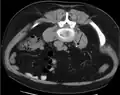

Calcium-containing stones are relatively radiodense (opaque to X-rays), and they can often be detected by a traditional radiography of the abdomen that includes the kidneys, ureters, and bladder (KUB film).[59] KUB radiography, although useful in monitoring size of stone or passage of stone in stone formers, might not be useful in the acute setting due to low sensitivity.[60] Some 60% of all renal stones are radiopaque.[61][62] In general, calcium phosphate stones have the greatest density, followed by calcium oxalate and magnesium ammonium phosphate stones. Cystine calculi are only faintly radiodense, while uric acid stones are usually entirely radiolucent.[63]

In people with a history of stones, those who are less than 50 years of age and are presenting with the symptoms of stones without any concerning signs do not require helical CT scan imaging.[64] A computed tomography (CT) scan is also not typically recommended in children.[65]

Otherwise a noncontrast helical CT scan with 5 millimeters (0.2 in) sections is the diagnostic method to use to detect kidney stones and confirm the diagnosis of kidney stone disease.[16][57][61][66][7] Near all stones are detectable on CT scans with the exception of those composed of certain drug residues in the urine,[59] such as from indinavir.

Where a CT scan is unavailable, an intravenous pyelogram may be performed to help confirm the diagnosis of urolithiasis. This involves intravenous injection of a contrast agent followed by a KUB film. Uroliths present in the kidneys, ureters, or bladder may be better defined by the use of this contrast agent. Stones can also be detected by a retrograde pyelogram, where a similar contrast agent is injected directly into the distal ostium of the ureter (where the ureter terminates as it enters the bladder).[61]

Renal ultrasonography can sometimes be useful, because it gives details about the presence of hydronephrosis, suggesting that the stone is blocking the outflow of urine.[59] Radiolucent stones, which do not appear on KUB, may show up on ultrasound imaging studies. Other advantages of renal ultrasonography include its low cost and absence of radiation exposure. Ultrasound imaging is useful for detecting stones in situations where X-rays or CT scans are discouraged, such as in children or pregnant women.[67] Despite these advantages, renal ultrasonography in 2009 was not considered a substitute for noncontrast helical CT scan in the initial diagnostic evaluation of urolithiasis.[66] The main reason for this is that, compared with CT, renal ultrasonography more often fails to detect small stones (especially ureteral stones) and other serious disorders that could be causing the symptoms.[14]